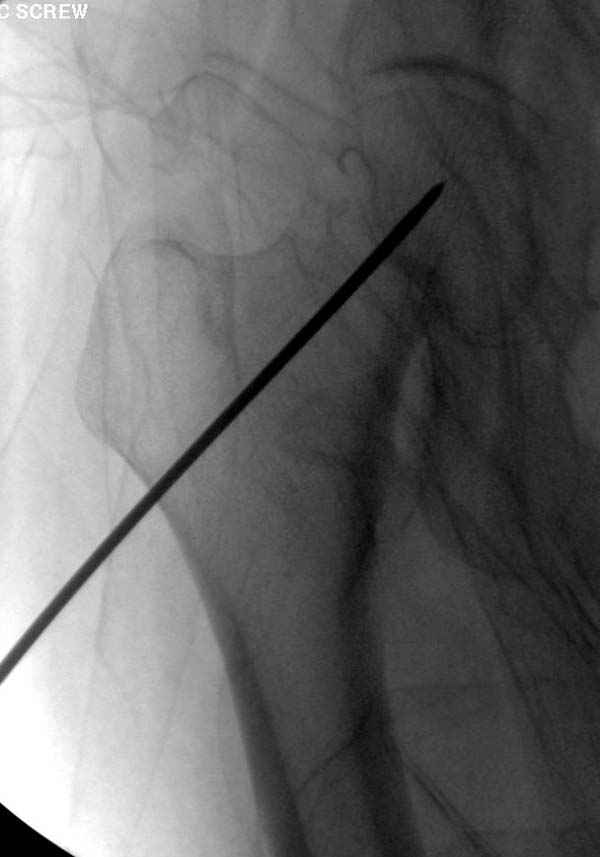

Re: неполный перелом шейки

“А что означает профилактическая перкутанная фиксация? Профилактика чего? Резорбции что ли? Снимки у Вас высокого качества- это ясно, а ППФ - это не ясно.”

Профилактику дальнейшего раскола неполного перелома шейки провели тремя канюлированными шурупами.